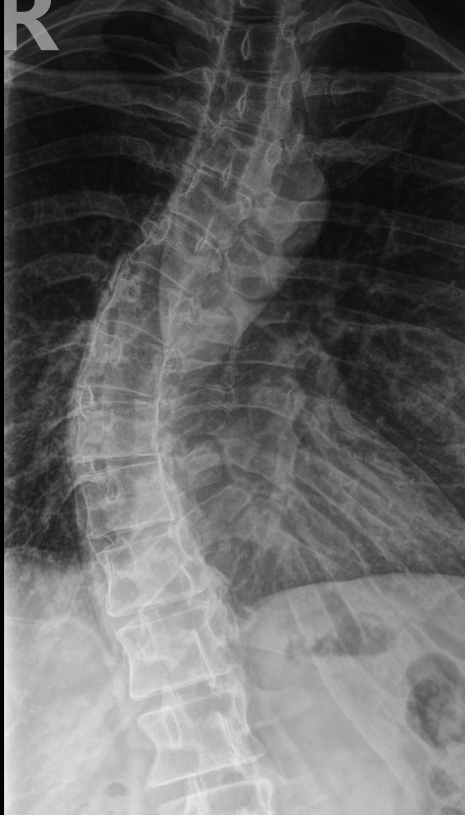

Scoliosis is a condition that affects the spine. It can make the spine curve sideways, and it can make it difficult to stand and move correctly. Scoliosis often happens during childhood, but it can also develop in adults. There are different types of scoliosis, and the cause is usually unknown. However, some cases of scoliosis are linked to conditions like cerebral palsy and muscular dystrophy.

Chiropractors use a variety of techniques to diagnose scoliosis, including:

• A physical examination

• X-rays

• MRI scans

• CT scans

• Scoliometer measurements.

This allows chiropractors to get a clear view of the curvature of the spine and identify any abnormalities.